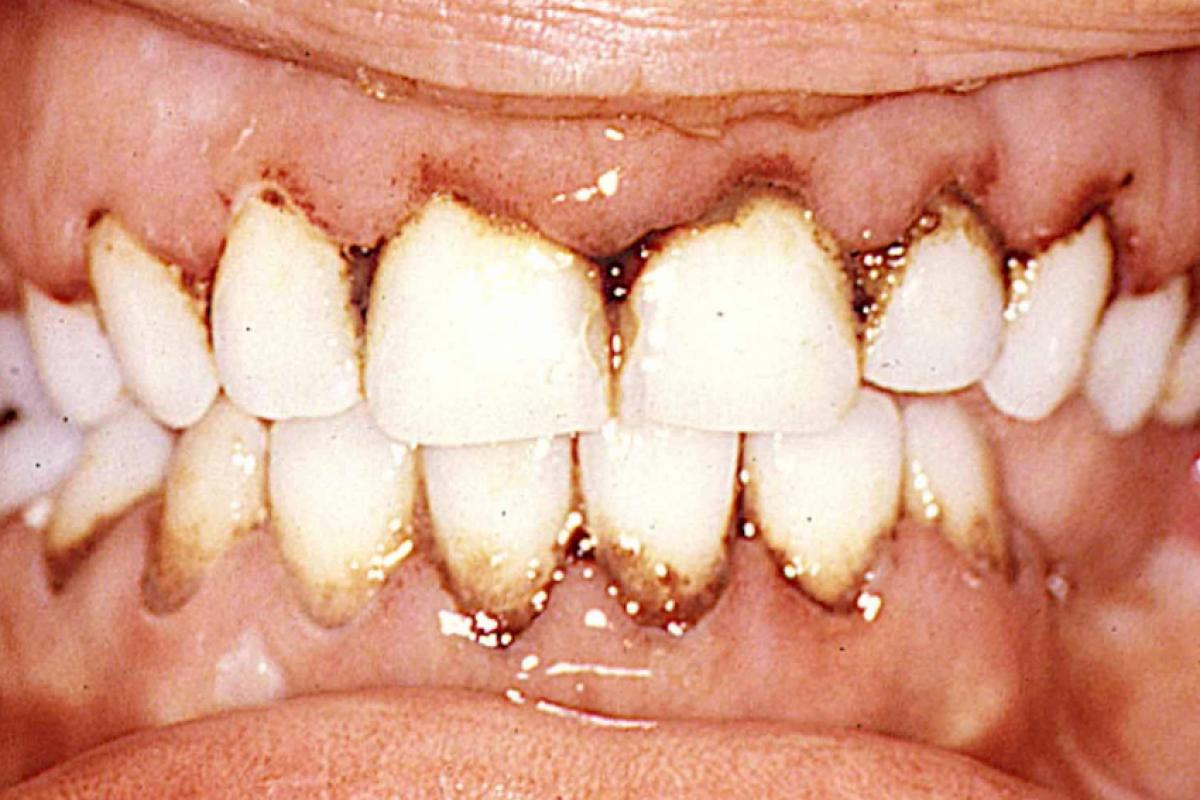

Leucemia na gengiva e o escorbuto

20.09.2025 09h50

COLUNISTA